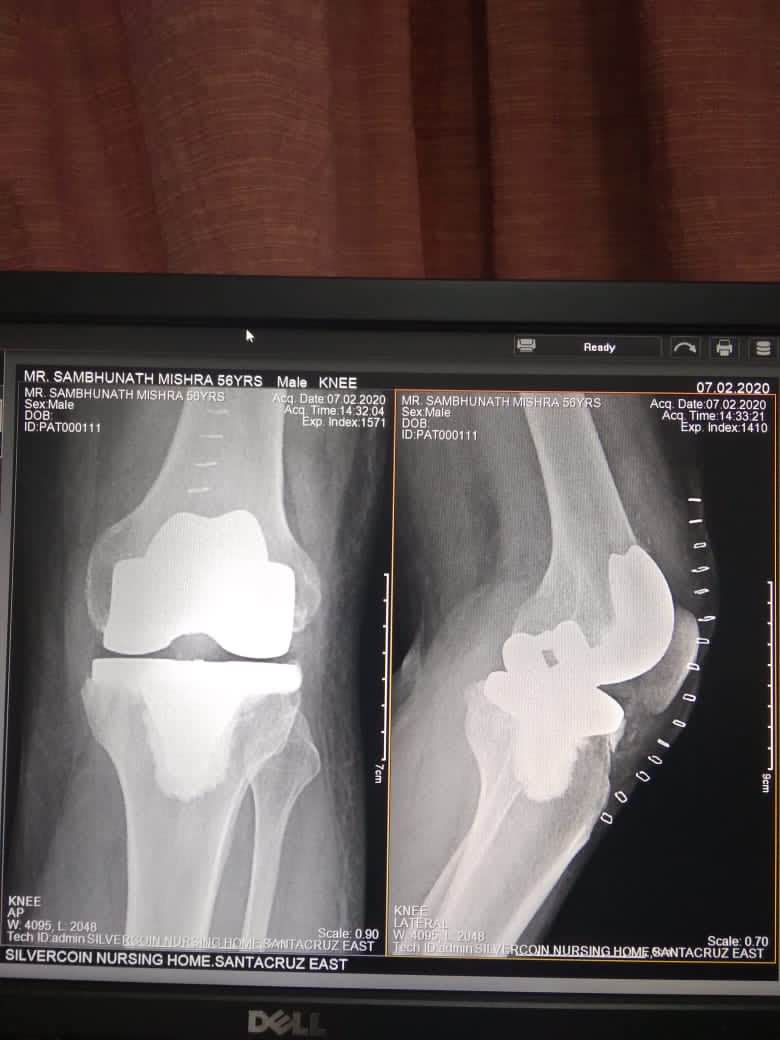

Best KNEE SURGEON in Andheri